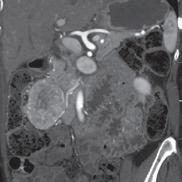

“This is a good example of a problem I’m having clinically that’s being solved by our research group,” says radiologist and scientist, Shane Wells, MD, Associate Professor of Radiology and Urology whose research focuses on improving diagnostic information to help urologists make more informed decisions. “I currently use ultrasound or CT to put needles into the liver to treat tumors. The needles get hot at the end and burn the tumor. It’s a minimally invasive procedure that can actually cure liver cancer and patients can go home the same day. However, one of the shortcomings of the current technology is that we can’t target tumors very well, which negatively affects patient outcomes. Now, the platform that we’ve developed at MIITT combines ultrasound and MRI to improve that tumor targeting.”

“One solution that we found is to use our Siemens MAGNETOM Free.Max 0.55T MRI Scanner,” says Dr. Seiberlich. As one of the few locations nationwide that owns and operates this “low field” machine, the MIITT team and UM Radiology have identified niche utilities, including the ability to conduct “in bore” biopsies--meaning the patient stays in the MRI scanner throughout the procedure. Now radiologists can clearly see the area that they want to biopsy, and accurately direct metallic needles without risk of damaging surrounding tissue. In addition to a wider bore, initially intended for larger patients or those with claustrophobia, the image quality of the scans is less affected by metal implants at low field strength. This is also advantageous when scanning patients with prior joint replacement surgery. “We can also capture MRI scans of parts of the body that are in motion, such as the heartbeat or blood flow,” she says. “Instead of a one second scan to make an image of a stationary body part, we can create a usable image in 20 milliseconds. We continue to discover special use cases that make this machine an exciting tool for us to have in radiology.”